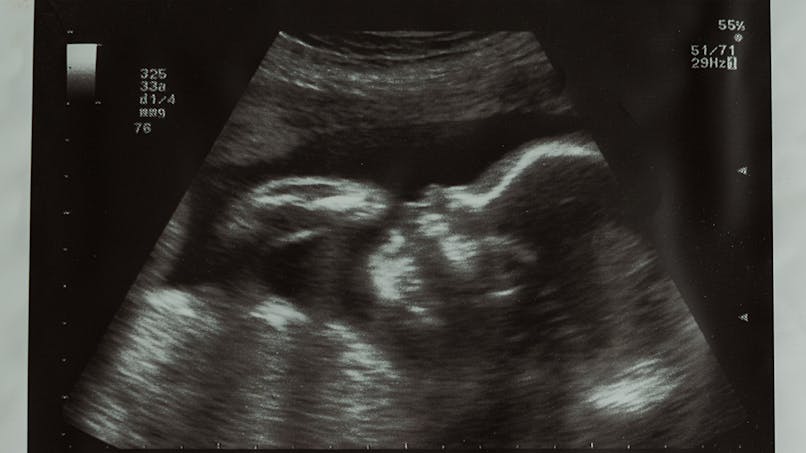

C'est la 22ème semaine de grossesse et le bébé mesure 26 cm Le poids du bébé à 24 sa est d'environ 500 g Avec un périmètre crânien d'environ 6 cm, sa tête est encore volumineuseBonjour, je viens de passer mon echographie morphologique a 22 sa le diametre du cervelet est a 18,4 mm plus petit que la moyenne qui est a 23 je dois repasser une echo dans 2 semaine que signifie cet ecart , est ce grave le medecin qui nous a passer l echo neEn cette ème semaine de grossesse, la taille du bébé de 22 SA est de 22,5 cm et son poids de 385 g Son corps est désormais beaucoup plus harmonieux, et bien que sa tête continue de se

Faitil la taille d'un grain de raisin, d'un citron ou d'un artichaut ? Déterminer la pointure enfant ou la pointure bébé adaptée Avec la moyenne établie par âge et par taille du pied, voici un tableau de correspondance des tailles de chaussures françaises en face des tailles britanniques et des tailles américaines Tranches d'âge Taille du pied en centimètres Taille française et UE Taille UKCertains de ces chiffres correspondent à la table des percentiles du fœtus ils vous indiquent comment votre bébé grandit Lorsque la future maman fait une échographie, les résultats ne sont pas toujours faciles à interpréter La plupart font référence aux percentiles et indiquent comment le fœtus se développe dans le ventre

A quoi ressembleratil dans les prochaines semaines ?Répondre 7 0 Voir la suite des commentaires WLe bébé à la SA 22 Pendant la semaine 22 d'aménorrhée le bébé mesure environ 28 centimètres des pieds à la tête, et pèse environ 475 grammes Son poids a beaucoup augmenté depuis la semaine dernière, ce qui est un indicateur de ce qui se passera à la prochaine étape

Taille et poids 22 sa Pour moi à 22 semaines SA, mon bébé pèse 557g pour 25 cm, l'échographe à même demandé s'il n'y avait pas eu d'erreur de datation mais non pas d'erreur juste un grand bébé ! A 22sa, le fémur était à 38 mm Voir plus Publicité Continuez de lire en dessous ezomz à 14h33 Alerter Copier le lien Le lien a été copié dans votre pressepapier Il me semble qu'il faisait 44mm à 23SA5 Je n'ai pas le compte rendu de l'écho sous les yeux mais il me semble que c'est bien ça Lorsque l'on est enceinte, il n'est pas rare de se demander quelle taille peut bien faire le petit être qui nous habite Et c'est bien beau de dire "la taille du foetus est de 3 cm", c'est

Resultats De Vos Echo Morpho C Est Ici Echographie Connaitre Le Sexe De Votre Bebe Forum Grossesse Amp Bebe Doctissimo